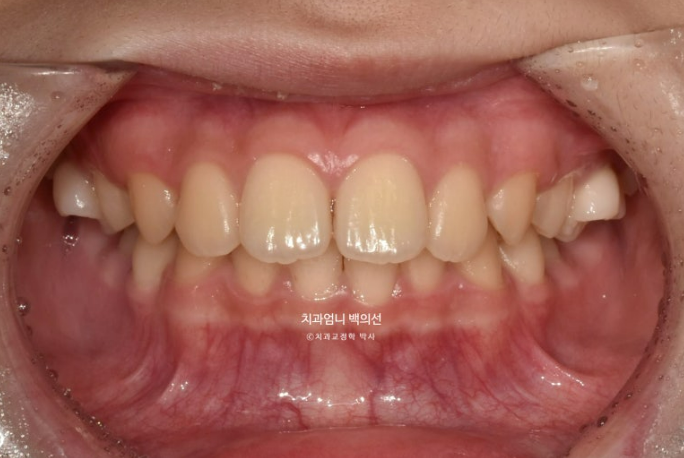

25.05

앞니 깊게 물리는 과개교합은 해결이 되었고 중심선은 잘 맞습니다.

어금니 교합은 1급 교합관계입니다.

결과가 성인교정에 준하는 만큼 유지장치도 성인교정에 준해서 들어갑니다.

과개교합 교정은 비베바를 하는 것이 좋지만 아직 제 2대구치 맹출중이라 인비절라인 투명유지장치 비베라는 맹출이 다 된 후 제작하기로 합니다.